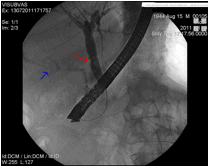

Η βασική ένδειξη της ERCP είναι η τοποθέτηση πλαστικής ή μεταλλικής ενδοπρόσθεσης (stent) για την αποσυμφόρηση του ίκτερου στις περιπτώσεις ανεγχείρητου καρκίνου της κεφαλής του παγκρέατος ή χολαγγειοκαρκινώματος, (δηλ καρκίνου του χοληδόχου πόρου, του κοινού ηπατικού πόρου, ή των πυλών του ήπατος). Η επιλογή του τύπου του stent εξατομικεύεται στον κάθε ασθενή. Σε γενικές γραμμές, τα πλαστικά stent αποφράσσονται από βακτηριδιακό υλικό ή ανάπτυξη του ίδιου του όγκου σε 3 μήνες κατά μέσο όρο, ενώ η βατότητα των μεταλλικών διαρκεί περισσότερο (περίπου 6 μήνες). Επίσης, υπάρχουν μεταλλικά stent μερικώς επικαλυμμένα για την αποφυγή της ανάπτυξης καρκινικού ιστού μέσα από τα κενά του πλέγματος τους (ingrowth). Επειδή τα μεταλλικά stent είναι πιο ακριβά, πρέπει να χρησιμοποιούνται μόνο στις περιπτώσεις που το προσδόκιμο επιβίωσης του ασθενούς είναι τουλάχιστον πάνω από 3-6 μήνες. Εικόνες  3 και 4.

Εικόνα 3. Ασθενής με εκτεταμένο χολαγγειοκαρκίνωμα Εικόνα 4. Τοποθέτηση πλαστικής

των πυλών του ήπατος (Klatskin tumor) και κλινική       ενδοπρόσθεσης (stent) στον προηγούμενο

εικόνα οξείας χολαγγειίτιδας.                                          ασθενή για την αποσυμφόρηση του ικτέρου και

της φλεγμονής πριν από τη χειρουργική

επέμβαση